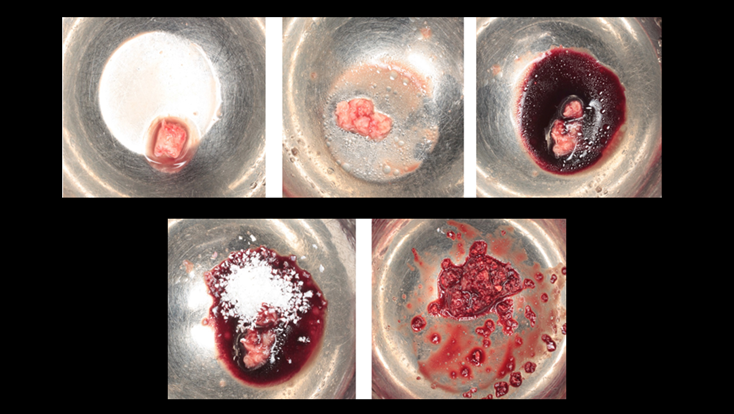

Clinical case: # 46 implant placement & GBR using i-Gen membrane for significant vertical resorption & mixed bone defect

- Courtesy of Dr. Iulian Filipov, Romania -

AnyRidge, mandibular posterior, i-Gen, resorption, bone defect, bone regeneration, space management, #46, GBR, Dr. Iulian Filipov

AnyRidge implant system, i-Gen